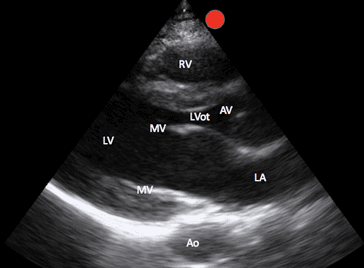

Es ist wichtig zu beachten, dass die konventionelle Echokardiographie zwar die Phased-Array-Sonde mit dem Bildschirmindikator (visualisiert als roter Punkt auf allen Bildern, die dieses Manuskript begleiten) links vom Patienten verwendet, diese Bilder jedoch auch mit der krummlinigen Sonde und der Phased-Array-Sonde erhalten werden können, die den Bildschirmindikator nach rechts vom Patienten zeigt. Die spätere Ausrichtung ergibt einfach ein 180-Grad-Spiegelbild der konventionellen Ausrichtung (Bild 1).

Gleiten Sie langsam einen Interkostalraum nach dem anderen nach unten, bis das PSL-Herzfenster sichtbar wird. Zu den Strukturen, die identifiziert werden können, gehören der rechte Ventrikel, der linke Ventrikel, der linke Vorhof, die Mitralklappe, die Aortenklappe, der Aortenausflusstrakt sowie die absteigende thorakale Aorta (Bild 3).

PSL-markierte Strukturen